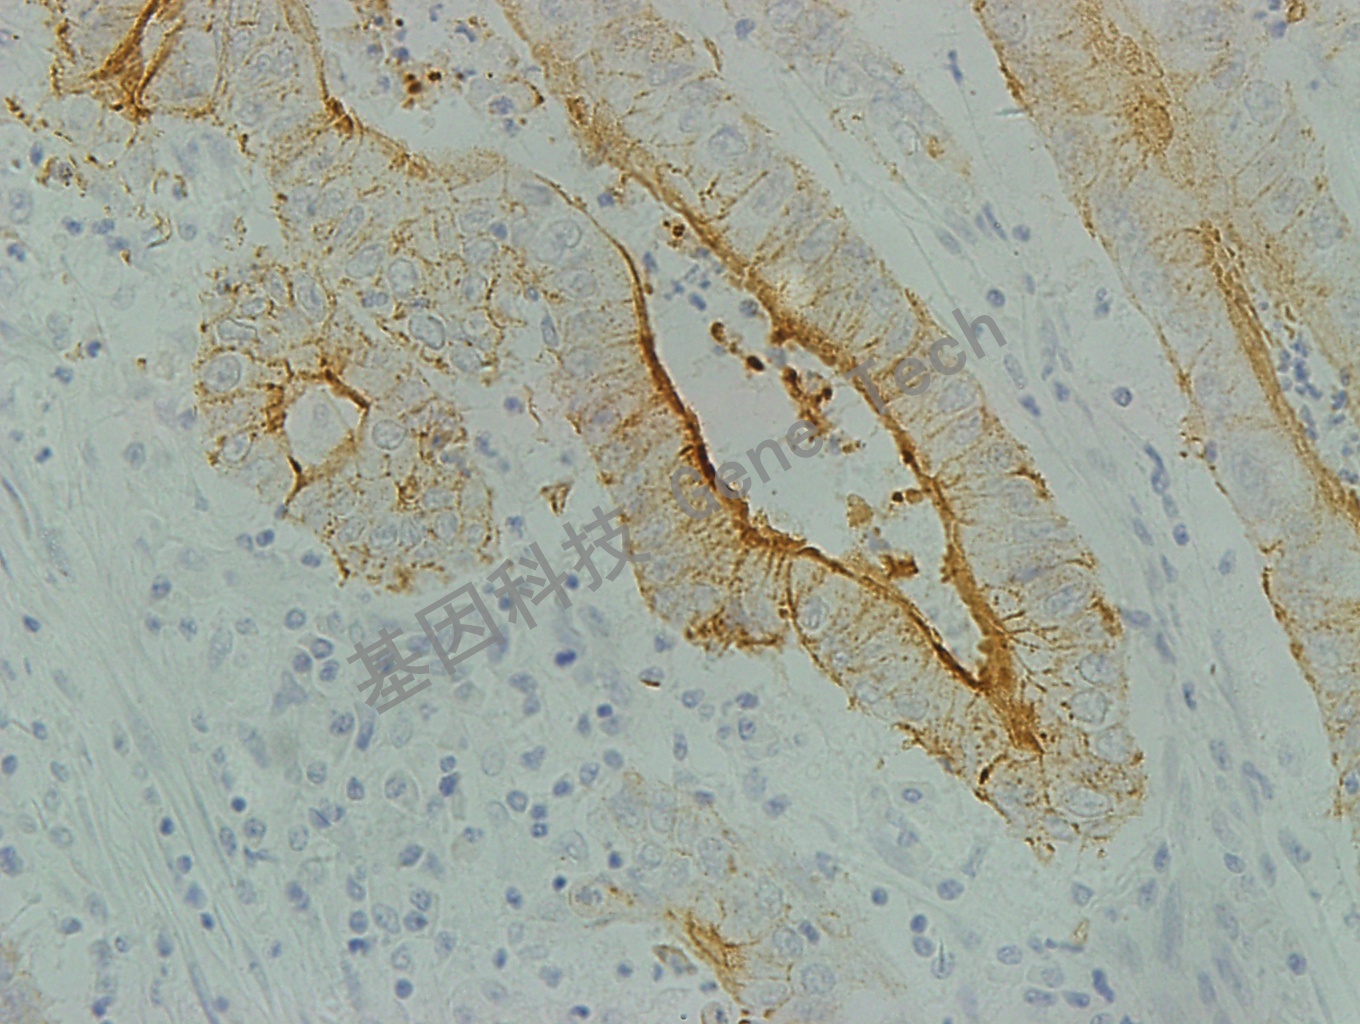

| 結(jié)腸癌石蠟切片,用Villin(GT2052)染色,細(xì)胞漿/刷狀緣陽(yáng)性,DAB顯色 | ||

| 預(yù)處理:高pH熱修復(fù) | 陽(yáng)性部位:細(xì)胞漿/刷狀緣 | 陽(yáng)性對(duì)照:小腸/結(jié)腸癌 |

| 簡(jiǎn)介:Villin(絨毛蛋白)是一種鈣依賴性肌動(dòng)蛋白結(jié)合蛋白,主要分布于腸上皮和腎近曲小管上皮的刷狀緣。該抗體是胰腺癌和胃腸道腺癌的特異性標(biāo)記物,幾乎100% 結(jié)腸腺癌表達(dá)陽(yáng)性。此外,在Merkel細(xì)胞癌、肺腺癌、卵巢癌及腎癌中,Villin也有不同程度的表達(dá)。 | ||